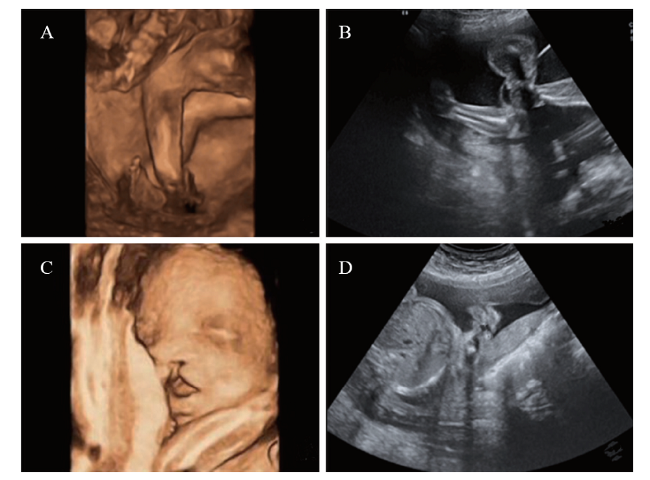

多维度联合超声检查检出胎儿外观畸形71例,检出率为92%。二维超声检查检出胎儿外观畸形56例,检出率为73%。多维度联合超声检查对胎儿外观畸形的检出率高于二维超声检查的检出率(2 = 10.316,P < 0.001),见表2。二维超声检查与多维度联合超声检查的典型胎儿外观畸形图像见图1

图1 二维超声检查与四维超声检查的典型胎儿外观畸形图像

A:1例足内翻胎儿超声检查的三维图像,立体显示内翻足的形态结构;B:同例足内翻胎儿超声检查的二维图像,可显示畸形但不直观,可作为测量数据的标准图;C:1例唇腭裂胎儿超声检查的四维图像,可动态立体显示胎儿唇部软组织的缺损;D:同例唇腭裂胎儿超声检查的二维图像,可显示畸形但不直观,可作为测量数据的标准图